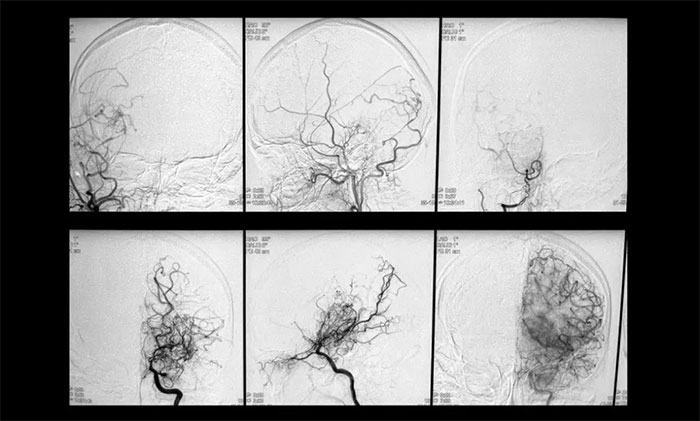

▲影像學(xué)檢查符合煙霧病特征

神經(jīng)外科6A病區(qū)專家團(tuán)隊(duì)為她完善了相關(guān)檢查,結(jié)果顯示:雙側(cè)頸總動(dòng)脈分叉處管腔中度狹窄,右側(cè)椎動(dòng)脈纖細(xì),異常小血管網(wǎng)狀聚集,符合“煙霧病”典型特征。